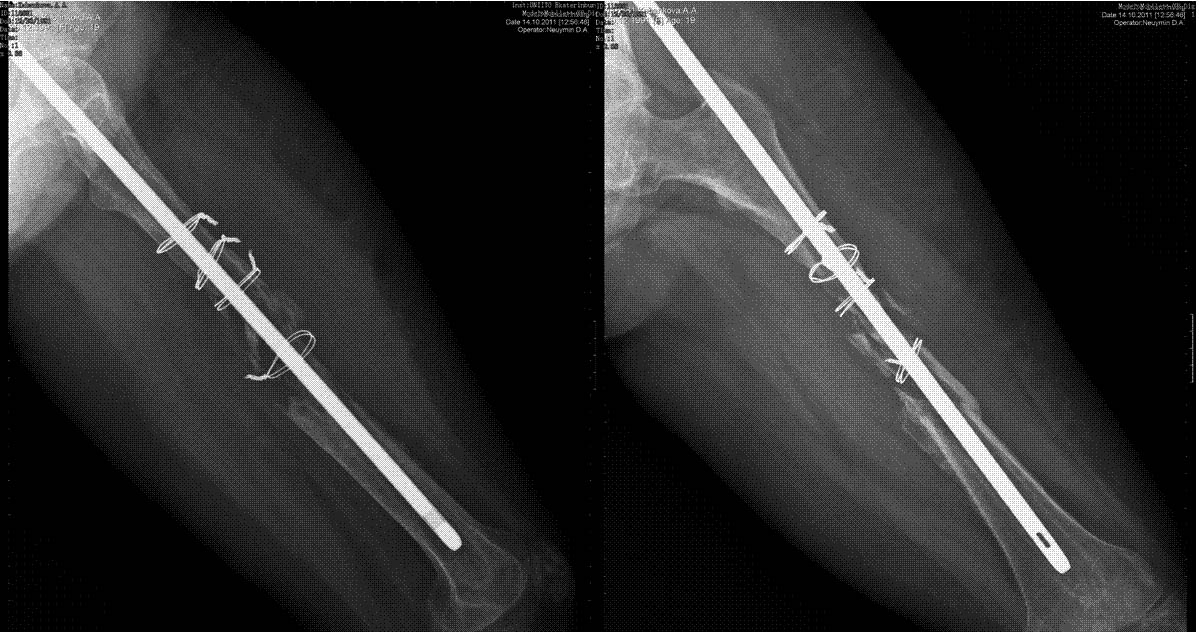

Уважаемые коллеги, выскажите пожалуйста свое мнение.пациентка 19 лет. выполнен

остеосинтез стержнем, в послеоперационном периоде лизирование кости между проволочными

петлями. у пациентки укорочение бедра 3,4см.+ дефект 10см.